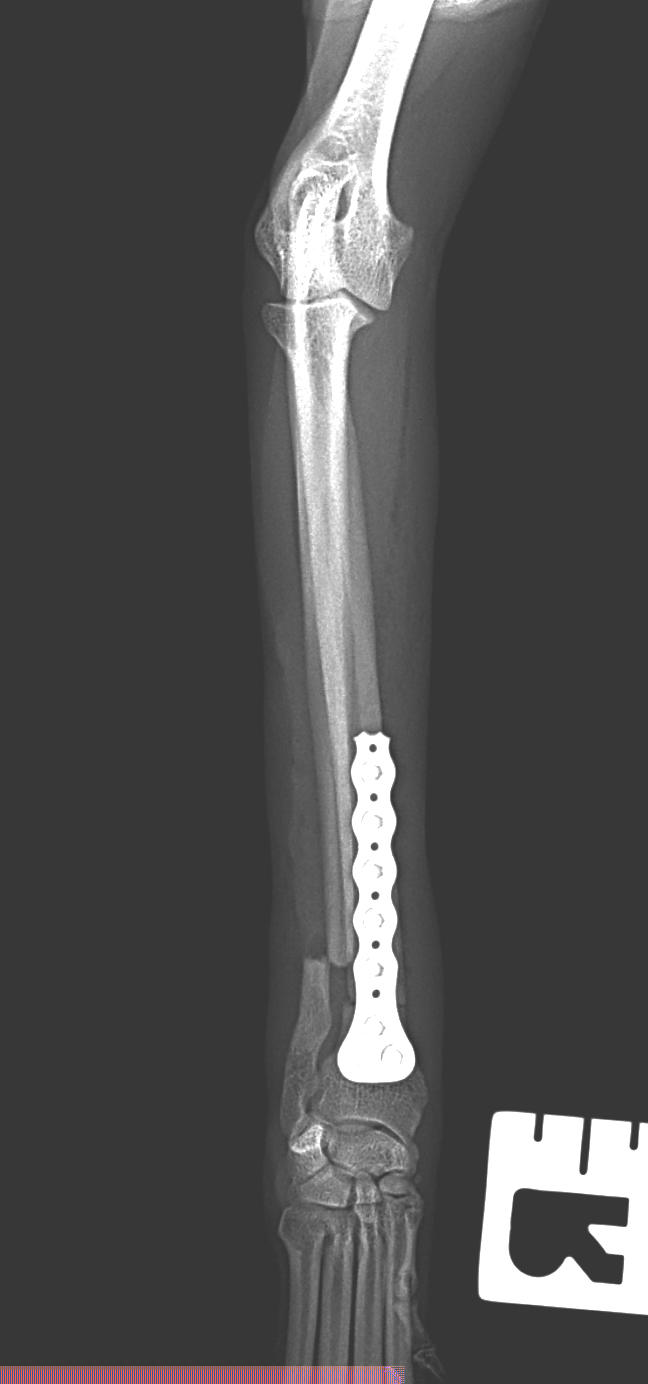

橈骨固定術 #248

小型犬が室内でジャンプして着地に失敗し、前肢を痛がり始めたとの事。かかりつけ医で橈尺骨遠位端骨折が確定されました。整復を目的に当院を受診されました。1.5 Titanium Locking Plateを用いて固定術を行いました。しばらく安静が必要です。